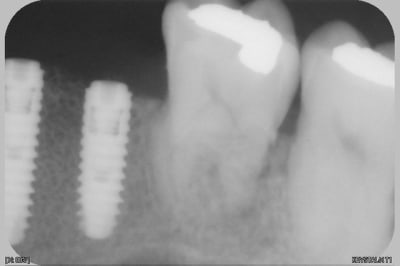

pas avant la semaine prochaine, je n'ai fait que des rétros.

à 8 jours et pano et rétro pour compenser la déformation du pano

--